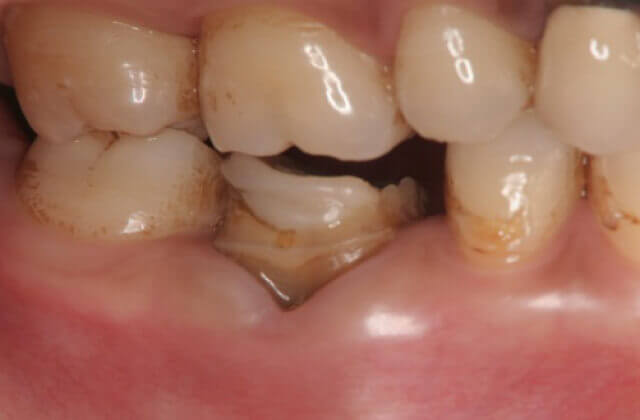

左記の症例のように歯が破折してしまう←ことがあります。これは、以前に歯医者さんで神経を抜いていた歯(無髄歯)に多く見られます。破折・亀裂が生じた歯は抜歯と判断されがちですが保存できる場合も多くあります。そのためには必要な検査を受け詳細な現状分析を行い正確な診断から最良の治療方法を選び確実にその治療を専門医が実践していくことで歯の寿命を長くできます。

数日前に腫れ、噛むと痛いため来院されました

歯肉剥離掻把治療を行い歯根が破折(矢印部分にヒビが入り割れている)している事を確認して破折線の接着による治療を行いました